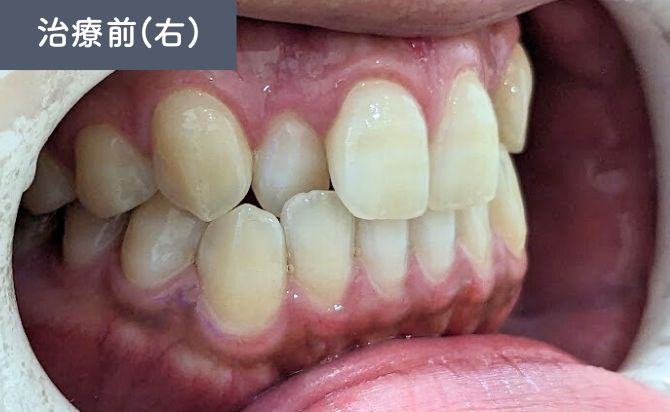

歯並びの変化(右)

咬合状態では、右側3番が切端咬合となっており、犬歯の誘導機能に影響を及ぼす可能性がある状態でした。

右側3番の切端咬合も改善し、犬歯誘導が適切に働く咬合状態となりました。上下のアーチ形態のバランスも改善し、見た目だけでなく、機能的にも安定した咬合が確立されています。